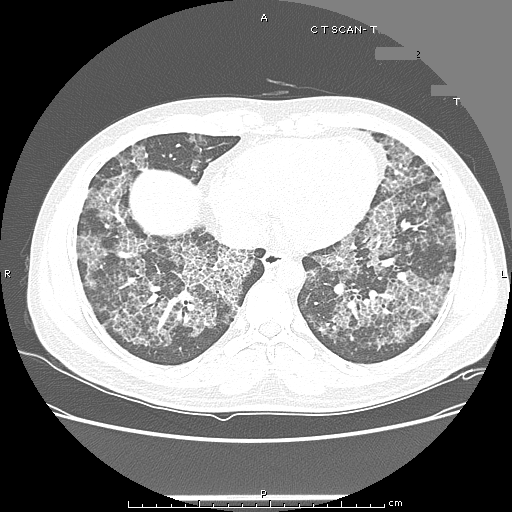

HRCT :

Ground-glass opacification, predominantly in a homogeneous distribution.

Thickened intralobular structures and interlobular septa in typical polygonal shapes, referred to as "crazy-paving“